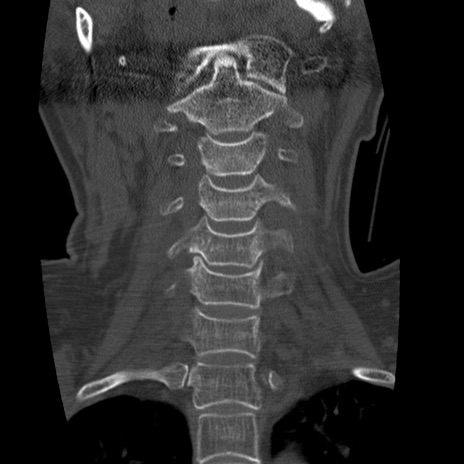

症例50 頚椎CT(冠状断像)

【症例】60歳代女性

【主訴】後頭部〜右後頸部にかけての痛み

【現病歴】本日飲食店でコーヒーを飲んでいたところ、突然後頭部〜右後頸部にかけて痛みが出現し、右上肢の感覚障害を伴ったため救急要請。

【身体所見】脳神経学的に明らかな異常所見を認めず。右上肢に軽度の感覚障害あり。

異常所見と診断は?